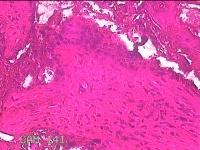

宫腔内容物

性别

女

年龄

28岁

临床诊断

不全流产?

一般病史

人流术后1月余,发现宫腔异常回声4天。

标本名称

大体所见

灰白暗红色不规则碎组织3x2.8x0.8cm一堆。

见胎盘绒毛。